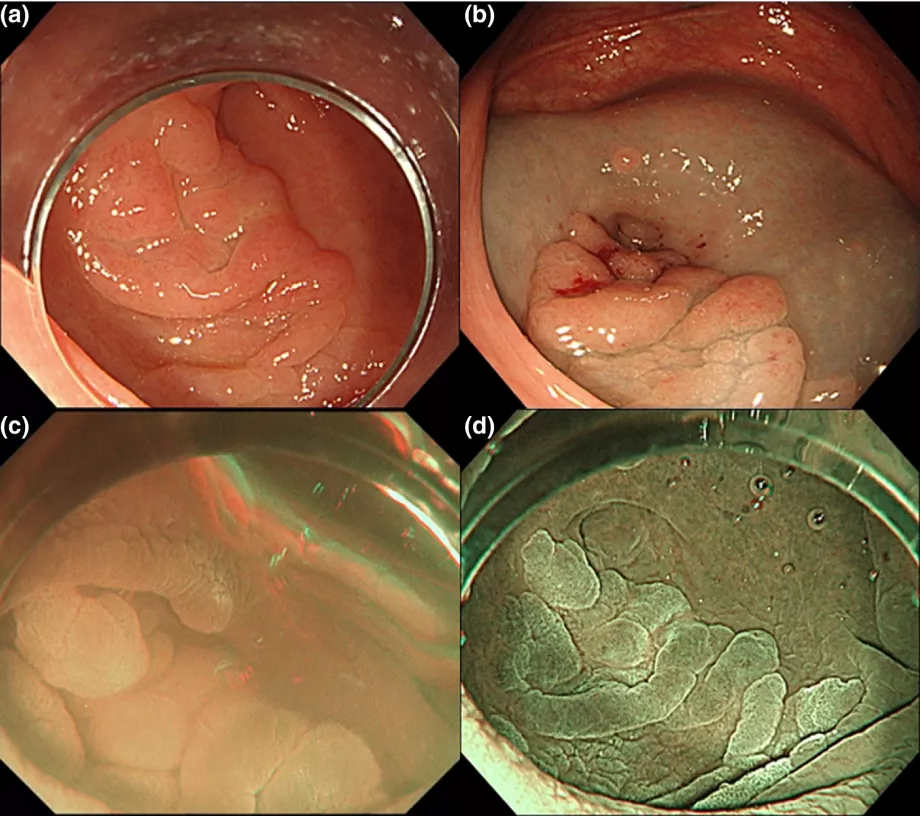

| Digestive Endoscopy (DEN): Kazunori Takada, Kinichi Hotta, Kenichiro Imai |

| Endoscopy: Xiao Li , Wengang Zhang , Fei Gao , Hao Dong , Jiafeng Wang , Ningli Chai , Enqiang Linghu |